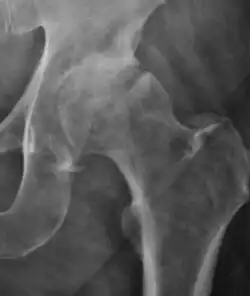

- Osteoarthritis

In adults, one of the main indications for radiographs is the detection of osteoarthritic changes (Figure 1(e)). Nevertheless, radiographs usually detect advanced osteoarthritis that can be graded according to the Tönnis classifications. The grading system ranges from 0 to 3, where 0 shows no sign of osteoarthritis. Intermediate grade 1 shows mild sclerosis of the head and acetabulum, slight joint space narrowing, and marginal osteophyte lipping. Grade 2 presents with small cysts in the femoral head or acetabulum, moderate joint space narrowing, and moderate loss of sphericity of the femoral head. Grade 3 is the severest form of osteoarthritis, which manifests as severe narrowing of the joint space, large subchondral cyst with productive bone changes that may lead to deformity of the bone components of the joint, while secondary osteoarthritis due to calcium pyrophosphate deposition can be diagnosed when calcification of hyaline cartilage and fibrocartilage is detected.[1]

There are other pathological conditions that can affect the hip joint and radiographs help to make the appropriate diagnosis. Acute bacterial septic arthritis can be diagnosed by radiographs when a fast regional osteoporosis and destructive monoarticular process develops (Figure 1(f)). In case of tuberculous or brucella arthritis it is manifested as a slow progressive process, and diagnosis may be delayed.[1]